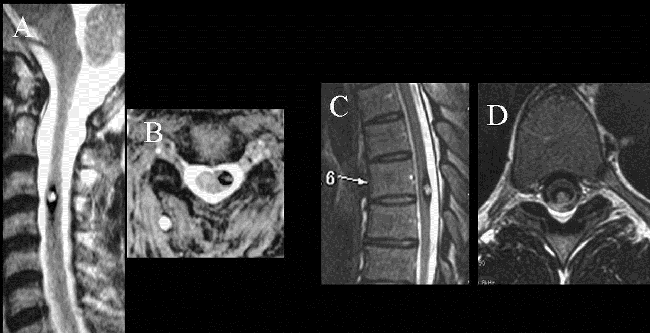

髓内海绵状血管瘤具有类似于其他颅内海绵状血管畸形的出血风险,治疗时应完全切除髓内海绵状血管畸形,以避免残留物复发和再出血。选择微小创伤方法(半椎板切除术),伴随术中超声检查,术中神经生理学监测和细致的显微外科技术,较大切除肿瘤的同时尽可能避免损伤脊柱功能和结构,术后疼痛较轻,患者可尽早进行康复训练,住院时间较短,术后脊柱不稳定性较椎板切除术减少。如今,半椎板切除术已广泛用于切除各种脊髓病变,包括髓内海绵状血管瘤。

半椎板切除术是于1992年较初为国际颅底脑干肿瘤手术教授德国巴特朗菲教授提出的、用于治疗脊柱内部出现的髓外病变。后为了尽可能地实现微创手术,巴特朗菲教授团队使用半椎板切除术作为髓内海绵状血管瘤的一种方法。

半椎板切除术主要根据髓内海绵状血管瘤的定位选择患者位置,患者在俯卧位进行手术。医生在病变区域通过标准方法,即通过背根入口区或中线脊髓切开术接近深部病变。除了精确的定位和脊髓的较好进入区域,解剖技术可能会影响髓内海绵状血管瘤的手术结果。手术过程中,使用双较钳和微型剪刀来断开引流血管是的重要。在确定手术平面后,应以锋利的解剖方式进行病灶表面周围的解剖,以避免正常脊髓组织的损伤。

(A-C)3D-CT扫描显示位于C1-2水平的髓内CM的术后图像。(B)在术中脊髓表面观察到含铁血黄素染色。(C)完全切除髓内CM,显示髓鞘切开的程度

巴特朗菲教授指出,显微镜可用来顺利地进行髓内手术切除,当创口较小化并且在精确的肿瘤位置进行切除时,这些损伤通常不会在切除期间出血。术中神经监测对神经外科医生有很大帮助,使其能够更精确地操作并且术后神经功能缺损的风险更低。由于髓内海绵状血管瘤通常位于脊髓的背面,因此,我们证明术中SSEP监测是监测此病手术中脊髓完整性的可靠手段。